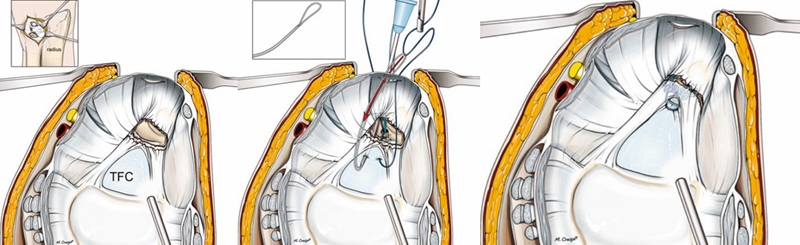

ⅠB型损伤手术治疗多采用缝合修复术。

TFCCⅡ型损伤,对症状持续存在,经保守治疗无效者可行腕关节镜手术。

ⅡA、ⅡB、Ⅱc型损伤:腕关节镜下清创术及软骨成形术;若合并尺骨撞击或尺骨正变异者,行关节镜下清创术结合尺骨头部分磨除术(Wafer术)。